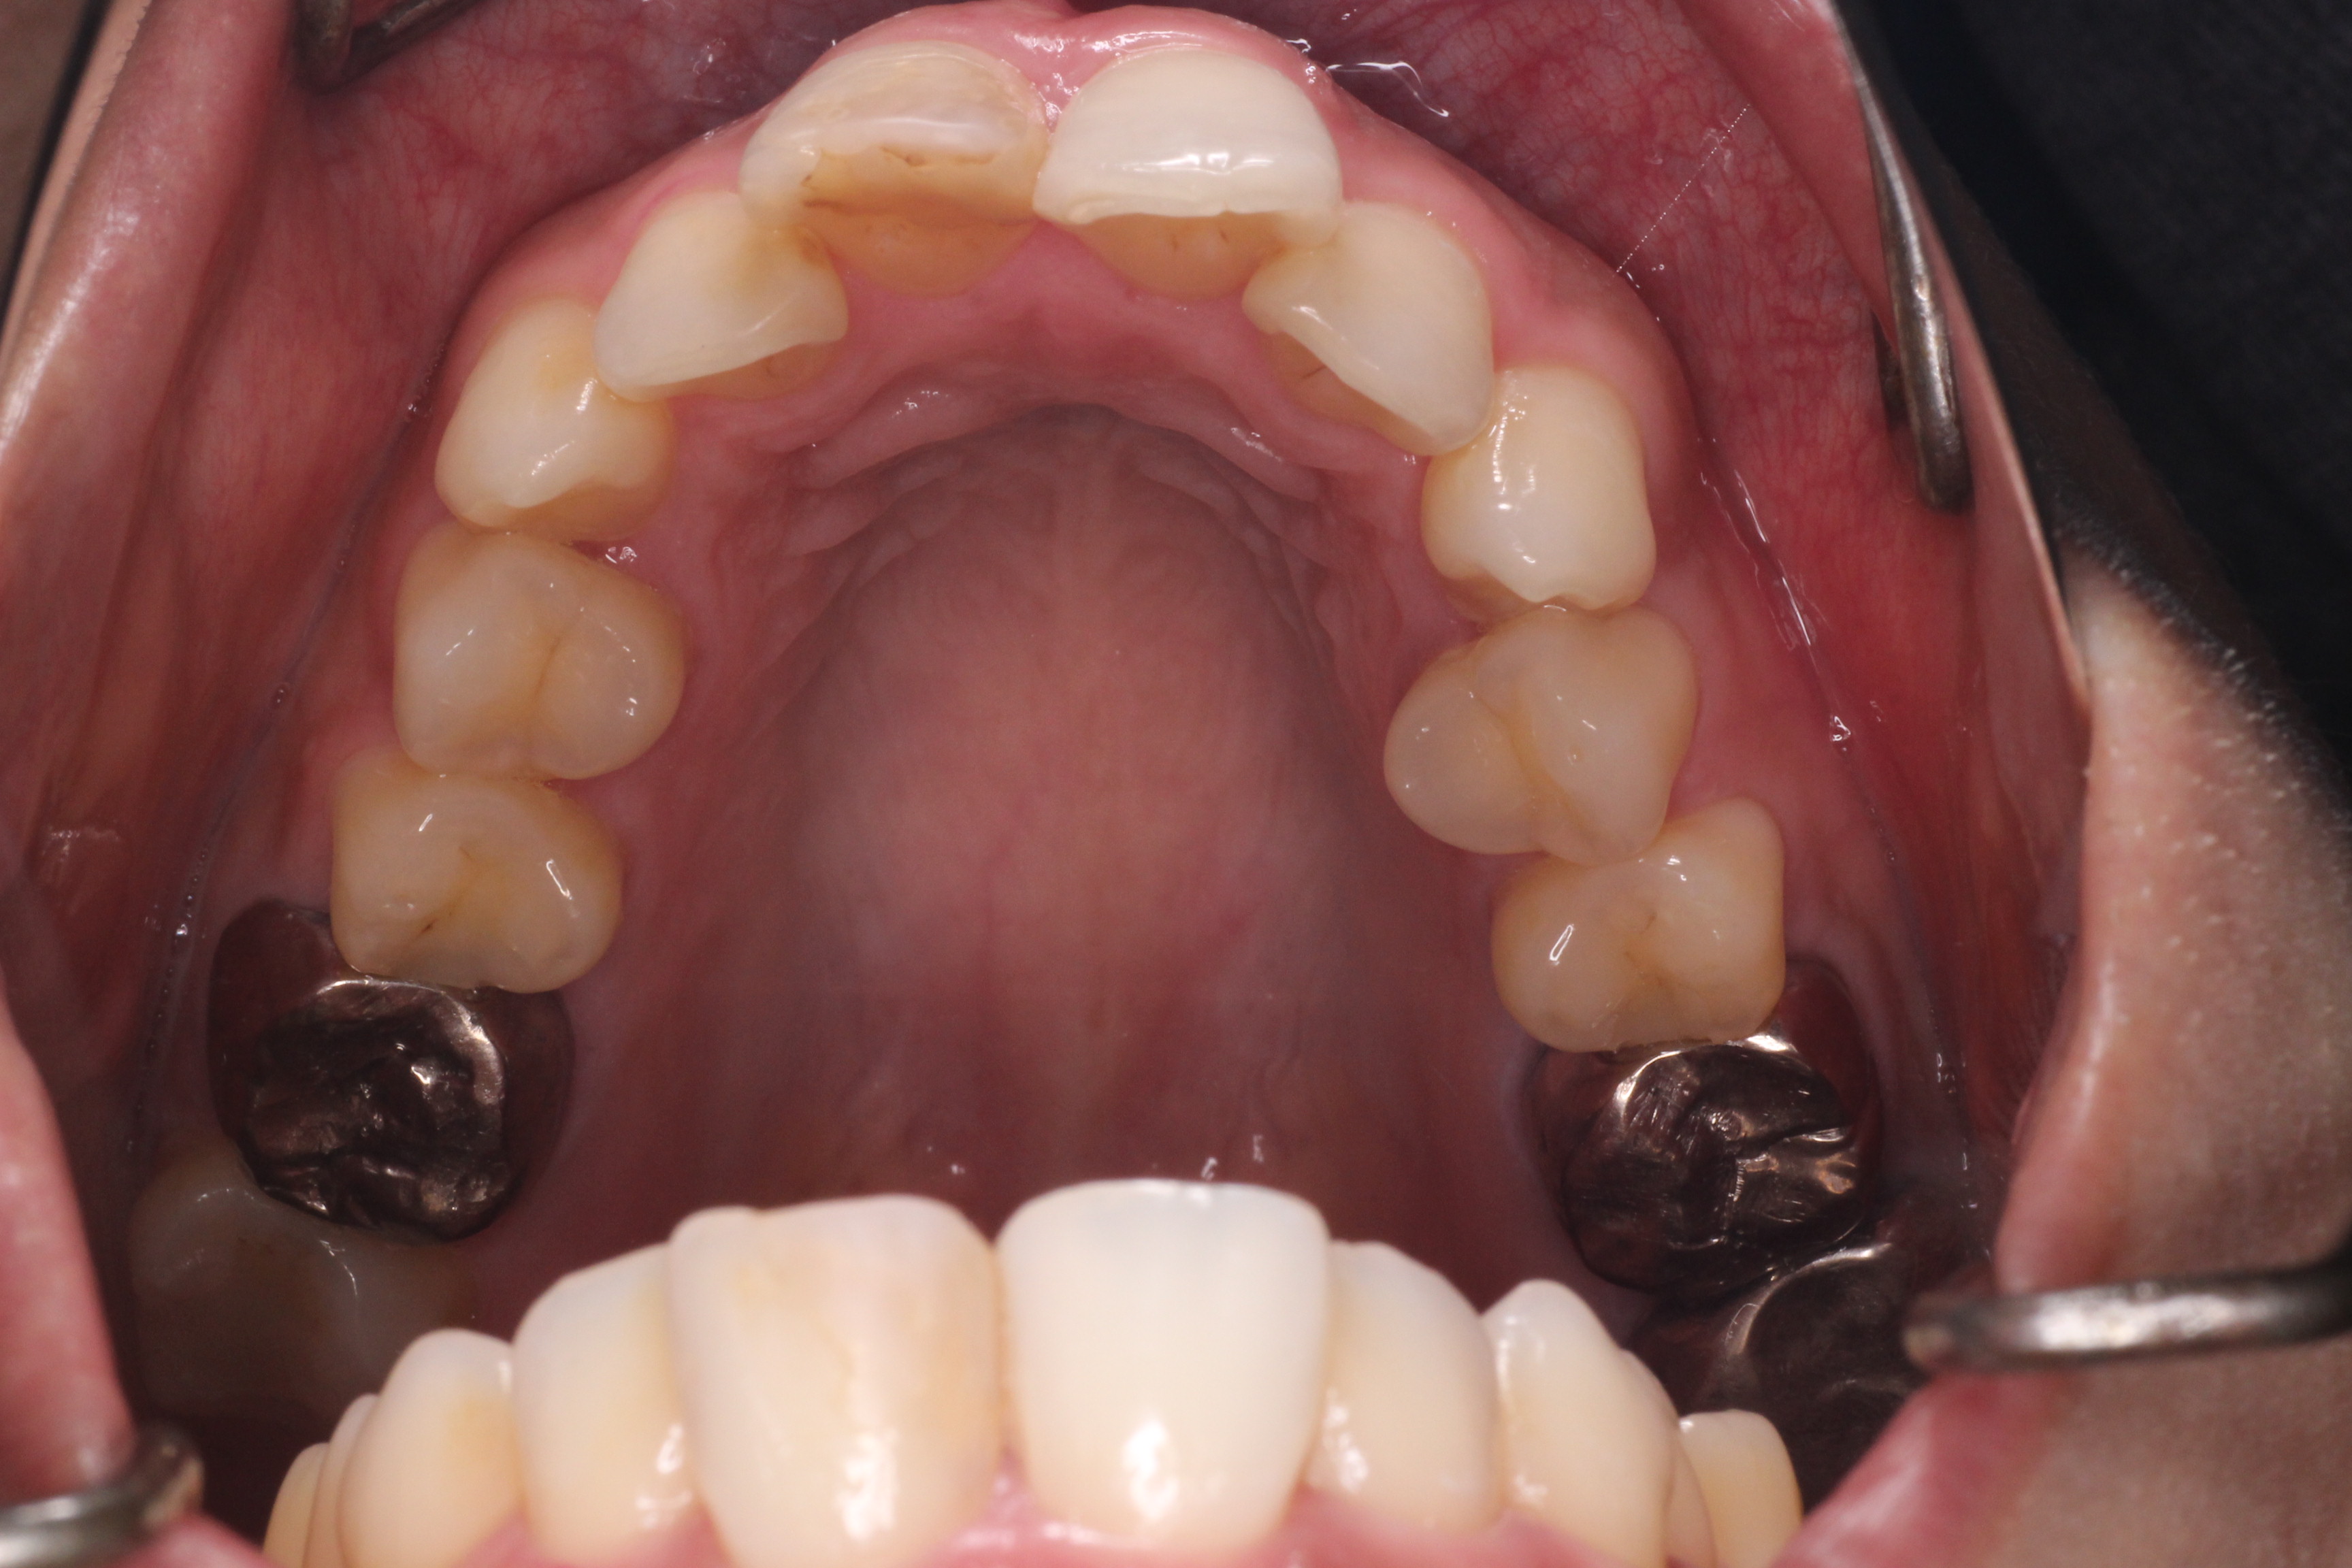

初診時の状態です。

初診時の奥歯の噛み合わせは上の歯と下の歯が1歯対1歯で噛めているので、奥歯はそのまま動かさず、

ねじれている前歯を動かしていきたいのですが、スペースがないので、そのスペースをつくらなければなりません。